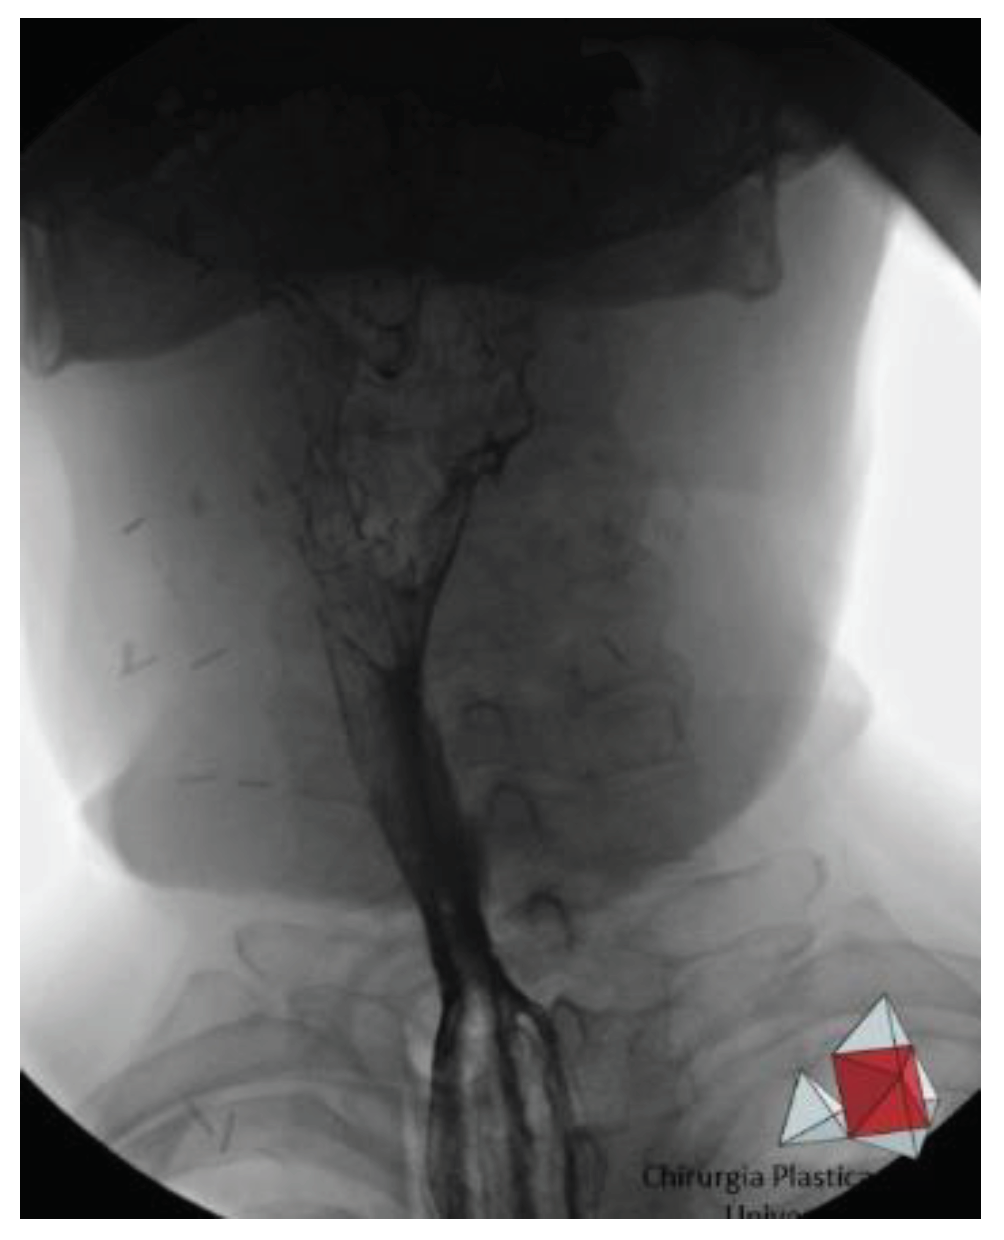

Patient are assessed for the presence of fistulas, esophageal strictures, and transit function via barium meal 30 days after surgery (

Figure 4).